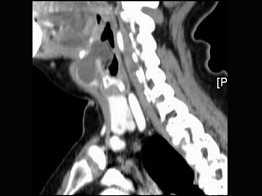

3.女,57歲,頸部不適,CT如圖所示,應診斷為  (    )

正確答案:C